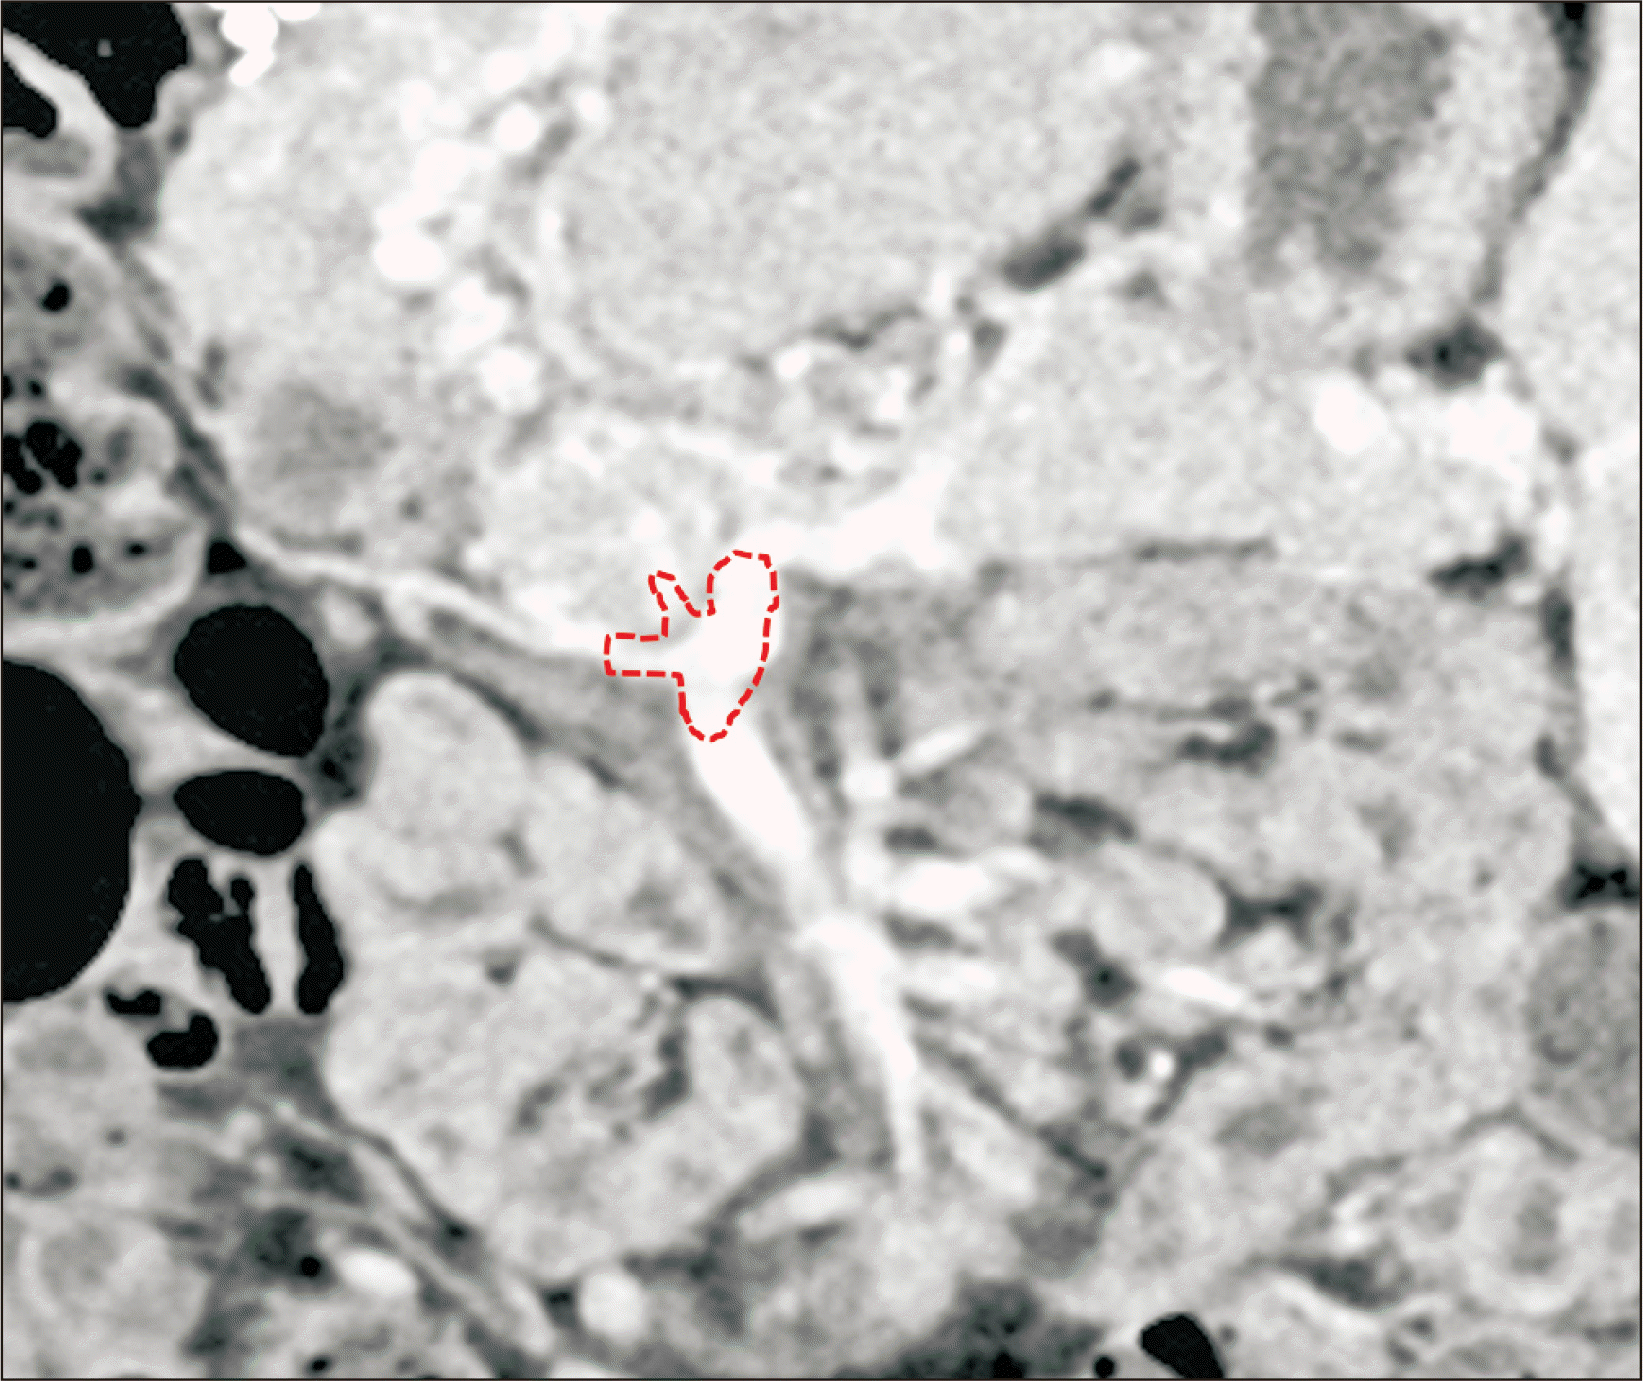

Figure 4

Preplanned design to obtain portal blood flow at the superior mesenteric vein-splenic vein confluence portion. A dotted circle indicates the boundary of vein conduit anastomosis.